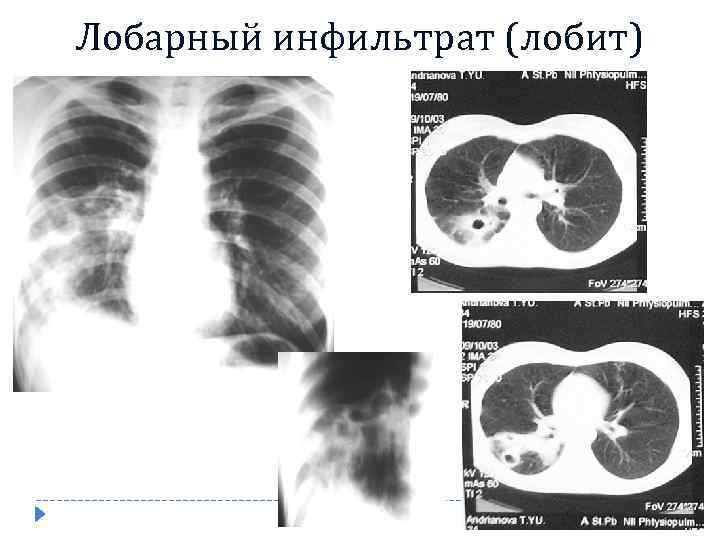

Лобарный инфильтрат (лобит)

Лобарный инфильтрат (лобит)